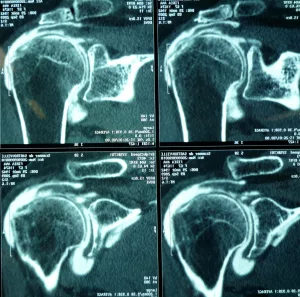

Bilan préopératoire ou Comment faire le diagnostic

L’examen clinique complet du patient par votre médecin permet d’évoquer le diagnostic (douleurs d’épaule nocturnes…), d’éliminer des lésions associées (fracture, capsulite rétractile,…) et de proposer un bilan complémentaire adapté (radiographie, échographie, arthro-scanner, IRM, arthro-IRM, électromyogramme).

Lorsqu’il existe une rupture de la coiffe des rotateurs, l’étendue des lésions dans le plan frontal (distale, intermédiaire ou rétractée à la glène), dans le plan sagittal (rupture complète ou incomplète, nombre de tendon atteint ; si ≥ 2 tendons = rupture massive), en épaisseur (rupture transfixiante ou partielle ; face profonde ou superficielle) doit être décrite de manière précise.

Par ailleurs, le bilan apprécie la qualité osseuse (ostéoporose, lacune osseuse) et musculaire (infiltration graisseuse).